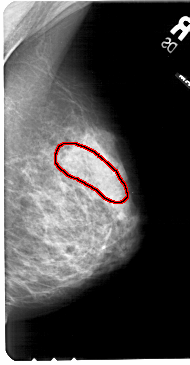

FILE: A_1677_1.RIGHT_MLO.OVERLAY

TOTAL_ABNORMALITIES 1

ABNORMALITY 1

LESION_TYPE CALCIFICATION TYPE PLEOMORPHIC DISTRIBUTION SEGMENTAL

ASSESSMENT 4

SUBTLETY 1

PATHOLOGY MALIGNANT

TOTAL_OUTLINES 1

BOUNDARY

RIGHT_MLO LINES 5461 PIXELS_PER_LINE 2836 BITS_PER_PIXEL 12 RESOLUTION 43.5 OVERLAY